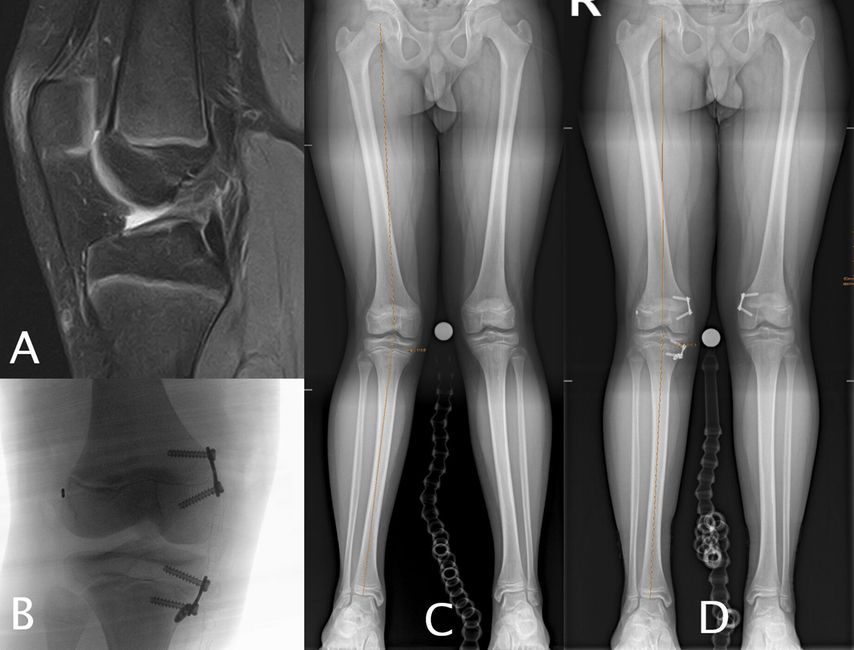

Abb. 1: 13-jähriger männlicher Fußballspieler mit VKB-Ruptur rechts (A), Valgusfehlstellung von 9° rechts aus dem distalen Femur (LDFA = 81°), proximaler Tibia (MPTA = 91°), Valgus von 5° Grad links primär aus dem distalen Femur (LDFA 84°) (C). Erfolgte Hemiepiphyseodese am medialen distalen Femur und an der medialen proximalen Tibia rechts sowie VKB-Plastik (4-Strang-Semitendinosus-Graft) (B). Korrekturerfolg vier Monate postoperativ (D)